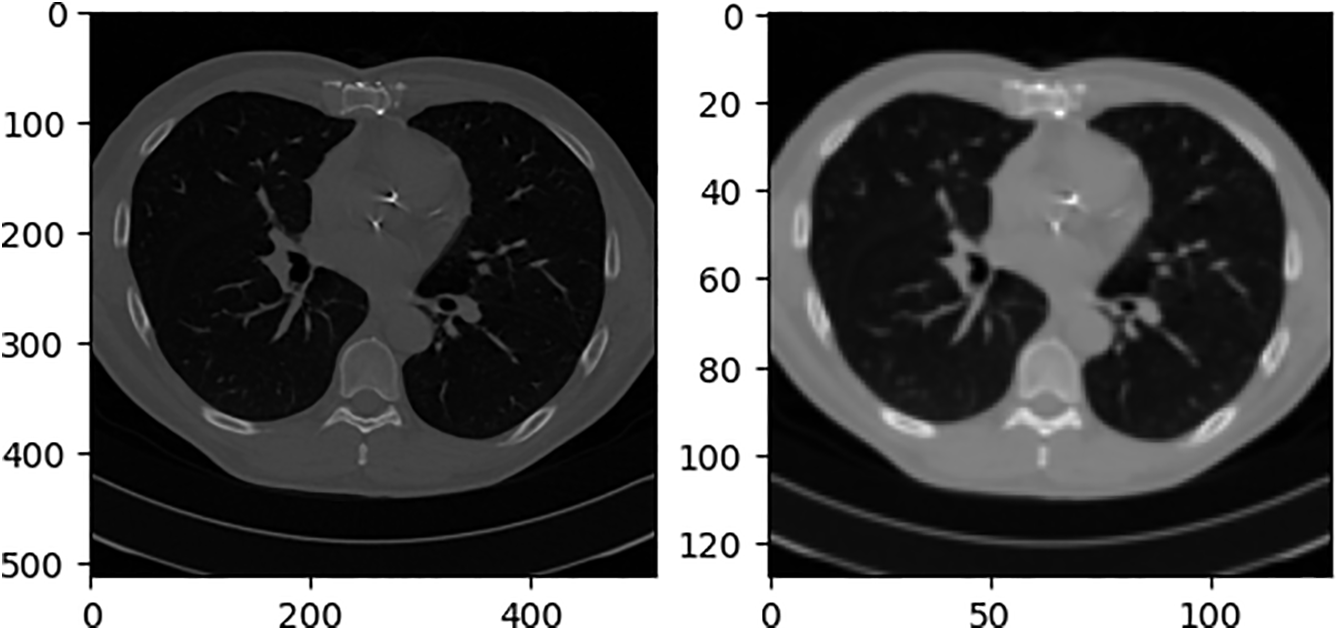

Our “virtual X-ray” images are standard DRRs generated by Siddon ray-casting directly on the CT voxel grid without any additional filtering or down-sampling. This technique is widely used in radiotherapy treatment-planning systems and has been validated against clinical radiographs in multiple studies [36,37]. Hence it is generally accepted as a surrogate for conventional projection X-ray. In this paper, we project from the front and sides of CT. During projection, if the projection resolution is too low, the projection image cannot be used and does not necessarily contain the entire CT content. If the projection resolution is too high, the content is excessive, the network input does not require a high-resolution image, and the projection calculation time is increased. After several projection experiments, the projection resolution of 180 × 200 can maximize the inclusion of the entire CT content and occupy as many pixels as possible. To distinguish real X-rays from simulated X-rays generated by the DRR algorithm, this paper refers to simulated X-rays as DRR images. The initial projection results are shown in Fig. 10.

Figure 10: Initial DRR image

As the input of the network, the ideal DRR image should only contain valid information and have the same size. The front projection Cor (Coronal plane) ratio is close to 1:1, while the side projection Sag (Sagittal plane) is obviously different. If the black pixels in the sag are deleted and the ratio is adjusted to 1:1, it will seriously destroy the information ratio on the lateral side of the thorax. The adjusted DRR image is not conducive to the convergence of the network, and it also does not match the distribution of the real human thoracic cavity, which increases the difficulty of generalizing the network to real X-rays. Fig. 11 shows the sag with the black border removed and the resolution adjusted from 180 × 200 to 128 × 128 compared to just the resolution.